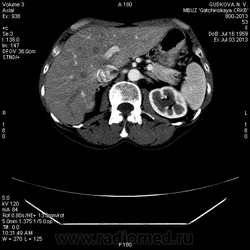

В артериальную фазу - интенсивное накопление контраста, как раз в области этого расширения, в 4-5 сегментах печени.Выше и ниже - идет неизмененная НПВ, без контраста (фаза артериальная!) В венозную фазу - небольшая гиперденсная зона перикавально в печени - и все.

На 3d-реконструкциях выглядит как кавернозная гемангиома, по форме напоминающая желчный пузырь (который я, кстати, не вижу, а УЗИсты описывают) Если это - ж.п., почему так интенсивно копит контраст, и вообще, расположение такое нетипичное?

Образование печени ли это вообще? Не перикавальное внепеченочное нечто? (и что?)

Это нижняя полая. Заброс контраста в нижнюю полую вену и контрастирование веточек портальной вены в артериальную фазу бывает при неправильной технике проведения болюса. Посмотрите тут: http://www.radiographia.ru/sites/default/files/abdominal_ct_protocols.pdf